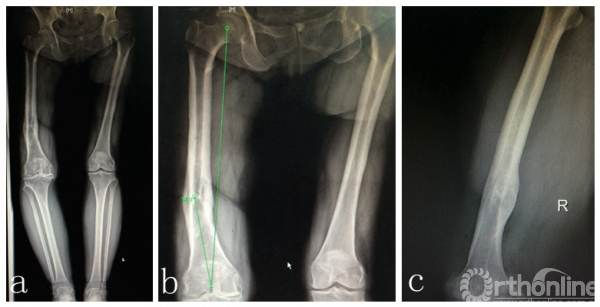

患者女性,69岁,病史7年。表现为逐渐加重的右膝关节疼痛、活动受限,负重行走和劳累后出现,上下楼梯更重,初始休息后可缓解,经口服硫酸氨基葡萄糖,非甾体类消炎药物,及“小针刀”,关节内注射玻璃酸钠等多种保守治疗,3年前疼痛、活动受限明显加重,影响日常生活就诊。23年前车祸伤致右股骨中下段粉碎骨折,外院行切开复位内固定,术后7月内固定松动,骨折未愈合,遂再次行切开复位内固定,髂骨取骨植骨术,直至骨折愈合后1年取出内固定。有高血压病史,规律服用降压药物控制良好。患者身高153cm,体重85公斤,BMI36kg/m2。右膝外上25cm术后瘢痕,右膝活动度10-90度,膝内外侧均有压疼,髌磨阳性。术前全长X片,膝关节负重正侧位片提示右膝关节重度骨性关节炎,右股骨中下段成角畸形(图1a,1b,1c)。

图1 a.双下肢全长片,右膝重度骨性关节炎,右股骨中下1/3陈旧骨折畸形愈合,向内侧成角畸形;

b.右股骨中下段内侧成角畸形,股骨外翻角约14度;c.矢状位显示股骨中下段无明显成角畸形。